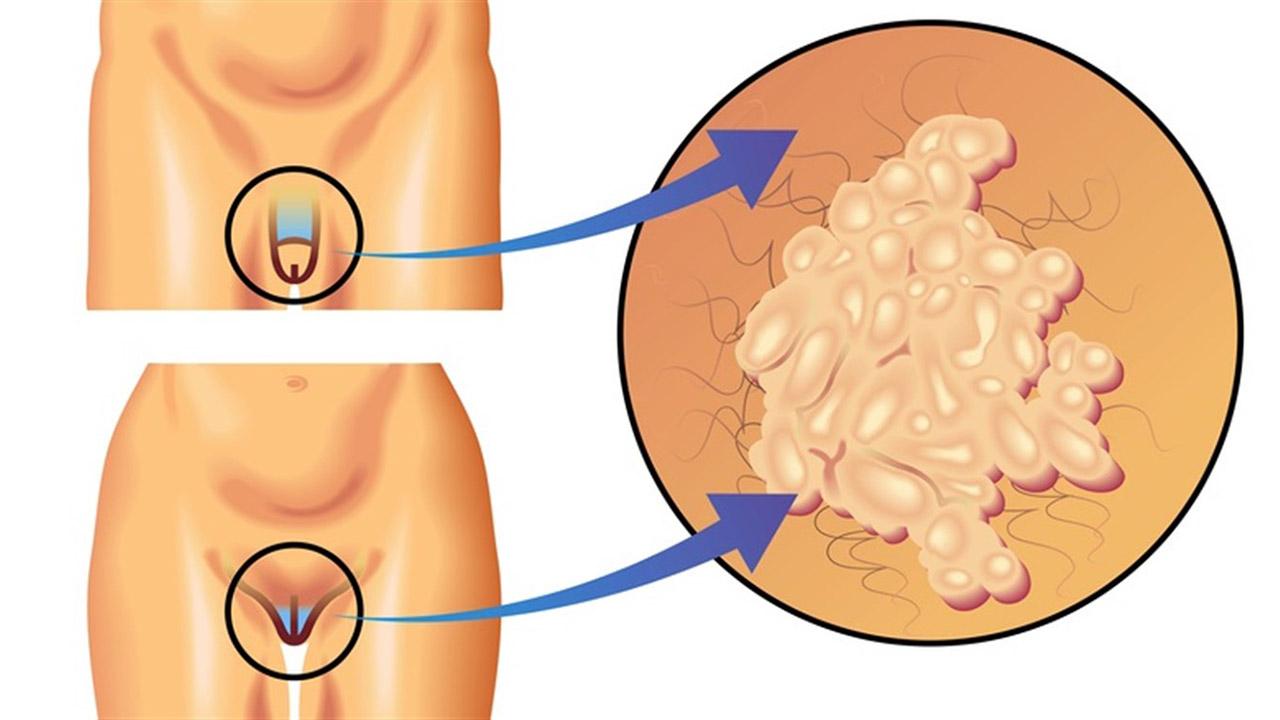

Кондиломы - это одно из самых распространенных заболеваний, передающихся половым путем. Они вызваны вирусом папилломы человека (ВПЧ) и могут появляться на внешних половых органах, анусе, ротовой полости и других областях тела.

Симптомы кондилом могут варьироваться, и визуальное представление этого заболевания может быть различным. Некоторые кондиломы выглядят как небольшие бугорки или бородавки, в то время как другие могут иметь форму плоских пятен или цветных наростов.